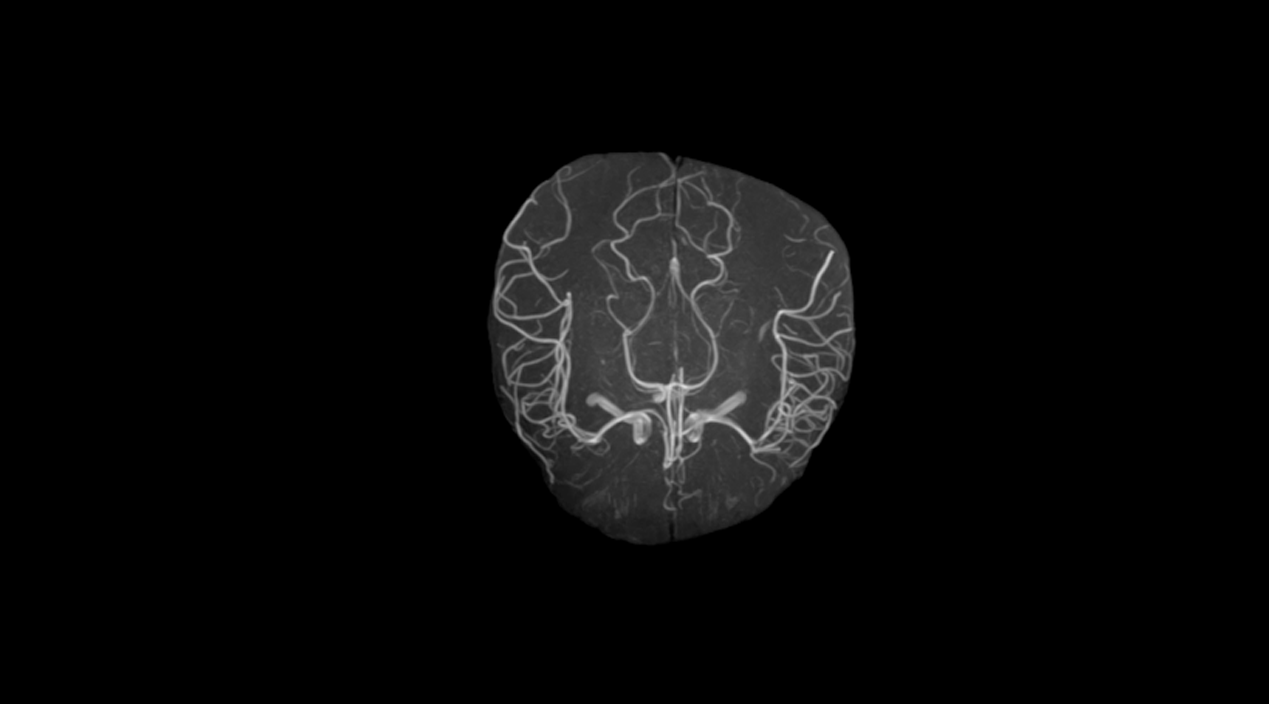

1.5T超导磁共振成像系统

魅影 Farol 1.5T

• 1.5T超导磁体技术:采用“零”挥发超导磁体技术;

• 精细匀场体系:采用精细匀场体系,使磁体的效能得到最大化的发挥;

• 16通道光纤射频信号数字传输技术:采样了先进的光纤射频信号数字传输技术,消除了磁共振信号在传输过程中造成的信号损失和失真;

• CS压缩感知加速功能:在保证图像质量的前提下极大的提高扫面速度

• 高性能梯度系统:采用最大强度达35mT/m的高性能梯度系统,极低涡流保证图像的清晰;